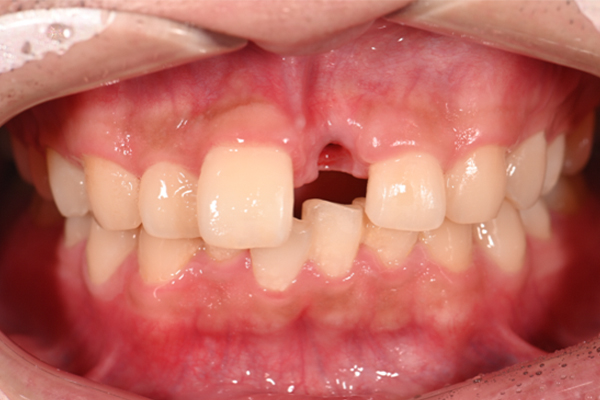

| 主訴 | 上の歯がぐらぐらする |

|---|---|

| 治療内容 | 上顎の歯が重度の歯周病のため全て抜歯し、

上顎に対するインプラント治療を行った。 午前中にインプラントの土台を入れ、夕方に上部構造(歯)を装着。 1日で噛めるようになる治療法。 |

| 治療期間 | 1日 |

| 治療費 | 250万円 |

| 治療 リスク | インプラント治療後2、3日はやや痛みを伴うことがあります。 |